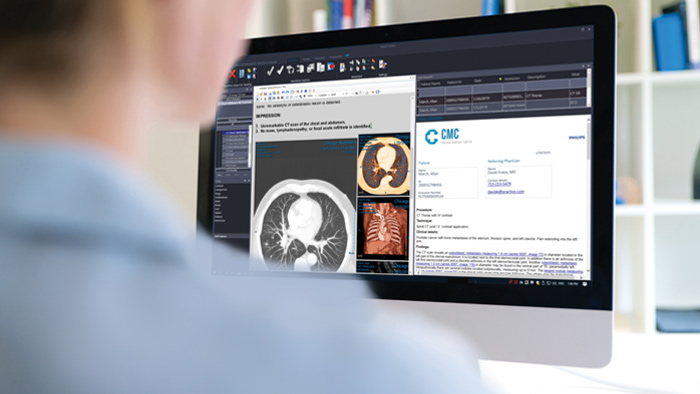

Proporciona un espacio de trabajo único con herramientas relevantes para leer con confianza y elaborar informes perspicaces, mejorando el flujo de trabajo y la productividad mediante el uso de funciones 3D nativas integradas e informes multimedia.

Vea cómo funciona Diagnostic Radiology Viewer